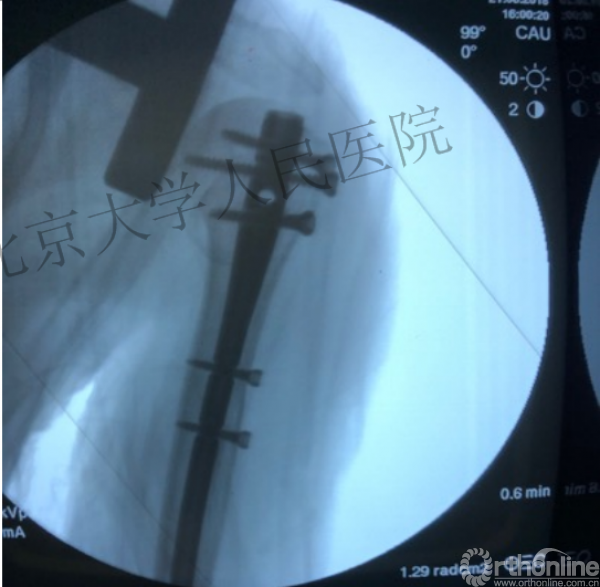

术中片

透视肱骨头正位、侧位确定进针点

复位良好的标准:颈干角:135°,大结节与肱骨头距离:8mm